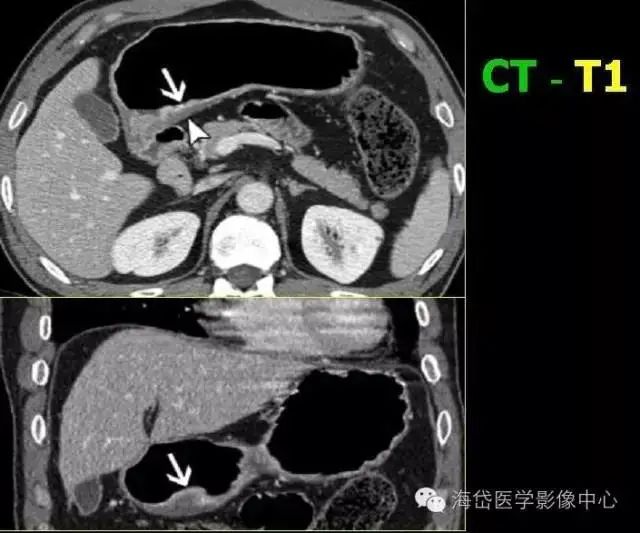

T1:低密度的粘膜層保持完整。

T2:胃壁增厚,低密度帶中斷,外輪廓光滑,周圍脂肪層清晰條索影少于1/3。

圖1 平掃+增強各期